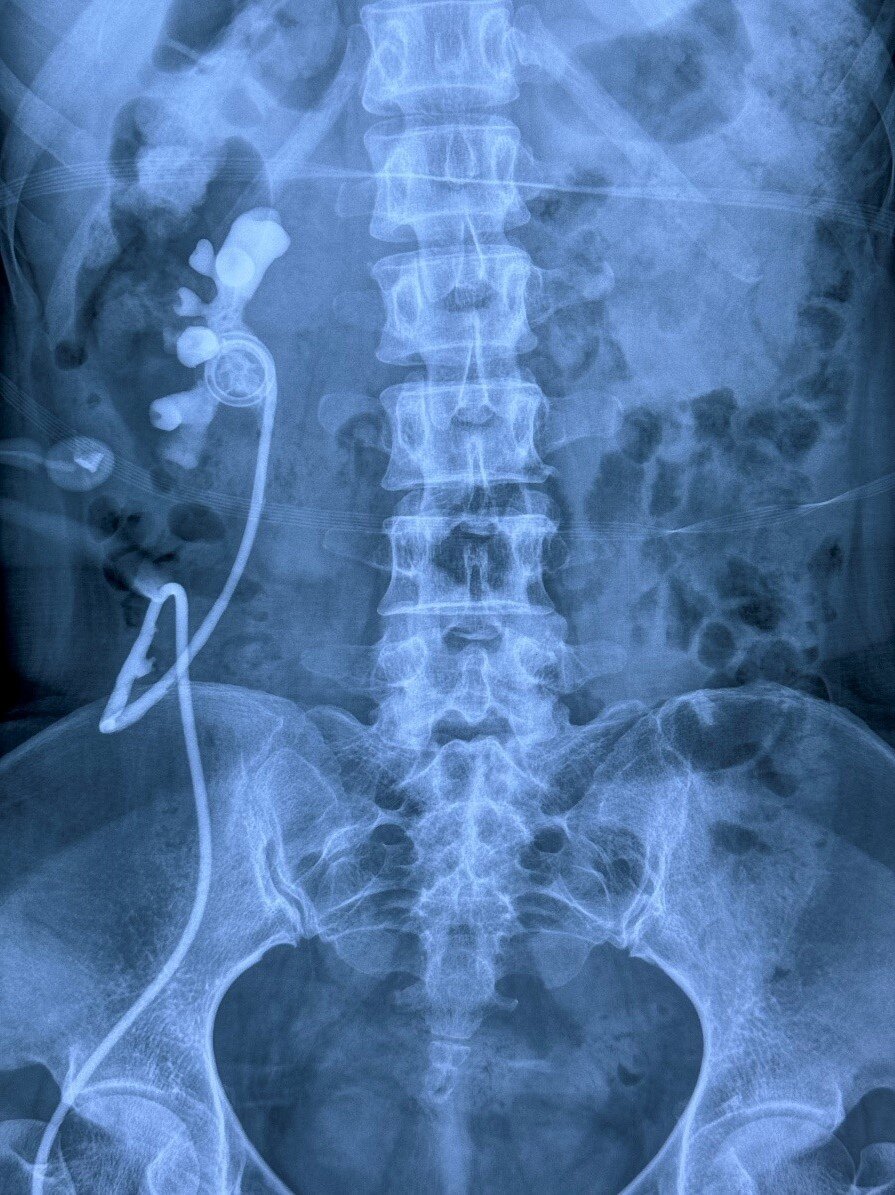

患者信息:女性,47岁,以“右输尿管皮肤造口半年”入院。患者半年前因盆腔右侧脓肿,在当地医院行子宫+右侧附件+阑尾切除术,术中发现输尿管下段损伤,随及行右侧输尿管皮肤造口至今,3月前在我院行右肾造瘘和顺行造影,现在右肾造瘘每天尿量约1000ml左右,如下图:

诊断:右输尿管皮肤造口术后,右肾造瘘术后

手术方式:机器人辅助腹腔镜膀胱翻瓣+右输尿管膀胱再植术

1. 术前评估考虑输尿管缺损较长,计划行右侧肠代输尿管手术,术中充分游离膀胱和右侧输尿管,尽可能保留输尿管末端段正常组织,发现输尿管回位后能到髂血管上方,距离膀胱4cm,随行膀胱翻瓣+输尿管再植。

2. 膀胱翻瓣+输尿管再植手术成功的关键在于吻合口两端的组织血供,梯形游离膀胱瓣,基底宽大,荧光造影显示吻合口两端血供良好。

3. 再植术后预防输尿管反流是主要问题,患者不能憋尿,勤排尿,定期随访,预防感染。